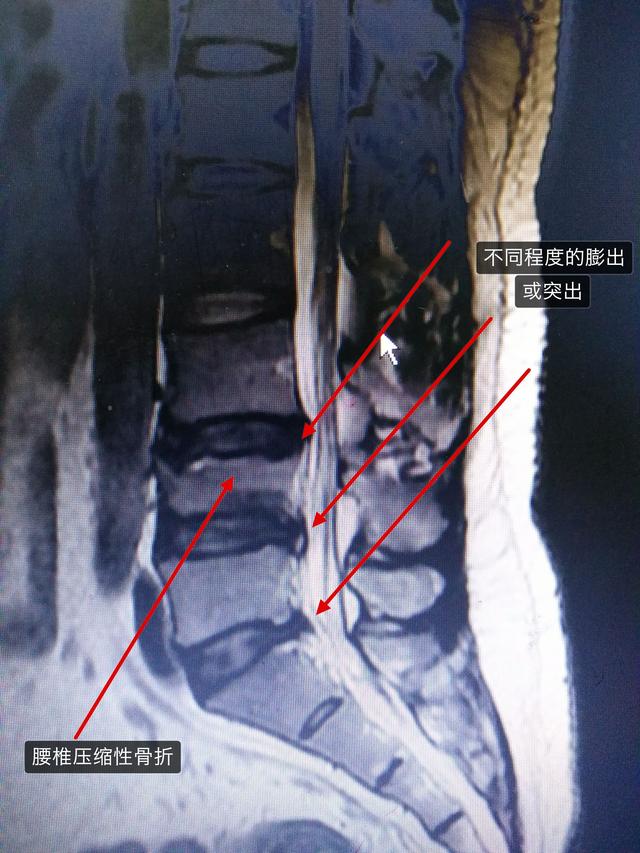

如果想确诊是否为腰椎间盘突出引起的,可以去医院拍腰椎的核磁共振。

如果长时间的脚趾麻木脚指头麻是怎么回事,而且两个脚不对称,首先考虑腰椎间盘突出压迫的神经根,引起的脚趾麻木。 一般能引起麻木的神经和血管卡压,单纯的两个脚趾麻木通常为神经卡压。...

神经卡压通常在腰椎,很少为局部卡压。

人体的脚趾的神经是从腰椎发出来的。